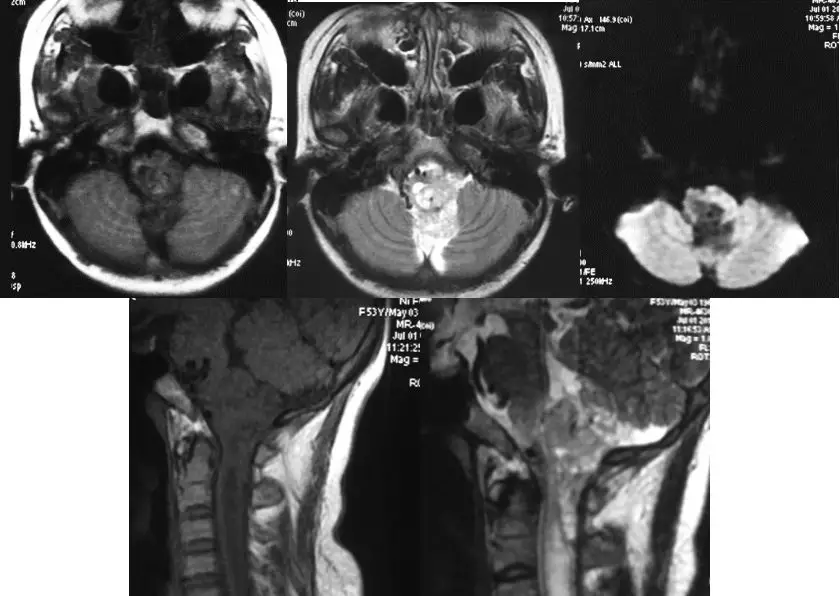

术前MR平扫提示颅颈交界区巨大占位,T1低密度,T2高密度,内有多量血管流空影。

增强MR提示病灶明显强化,伴瘤内血管影。除此以外,脑干侧方和腹侧可见扩张的静脉。

术前CTA同样提示肿瘤血供丰富